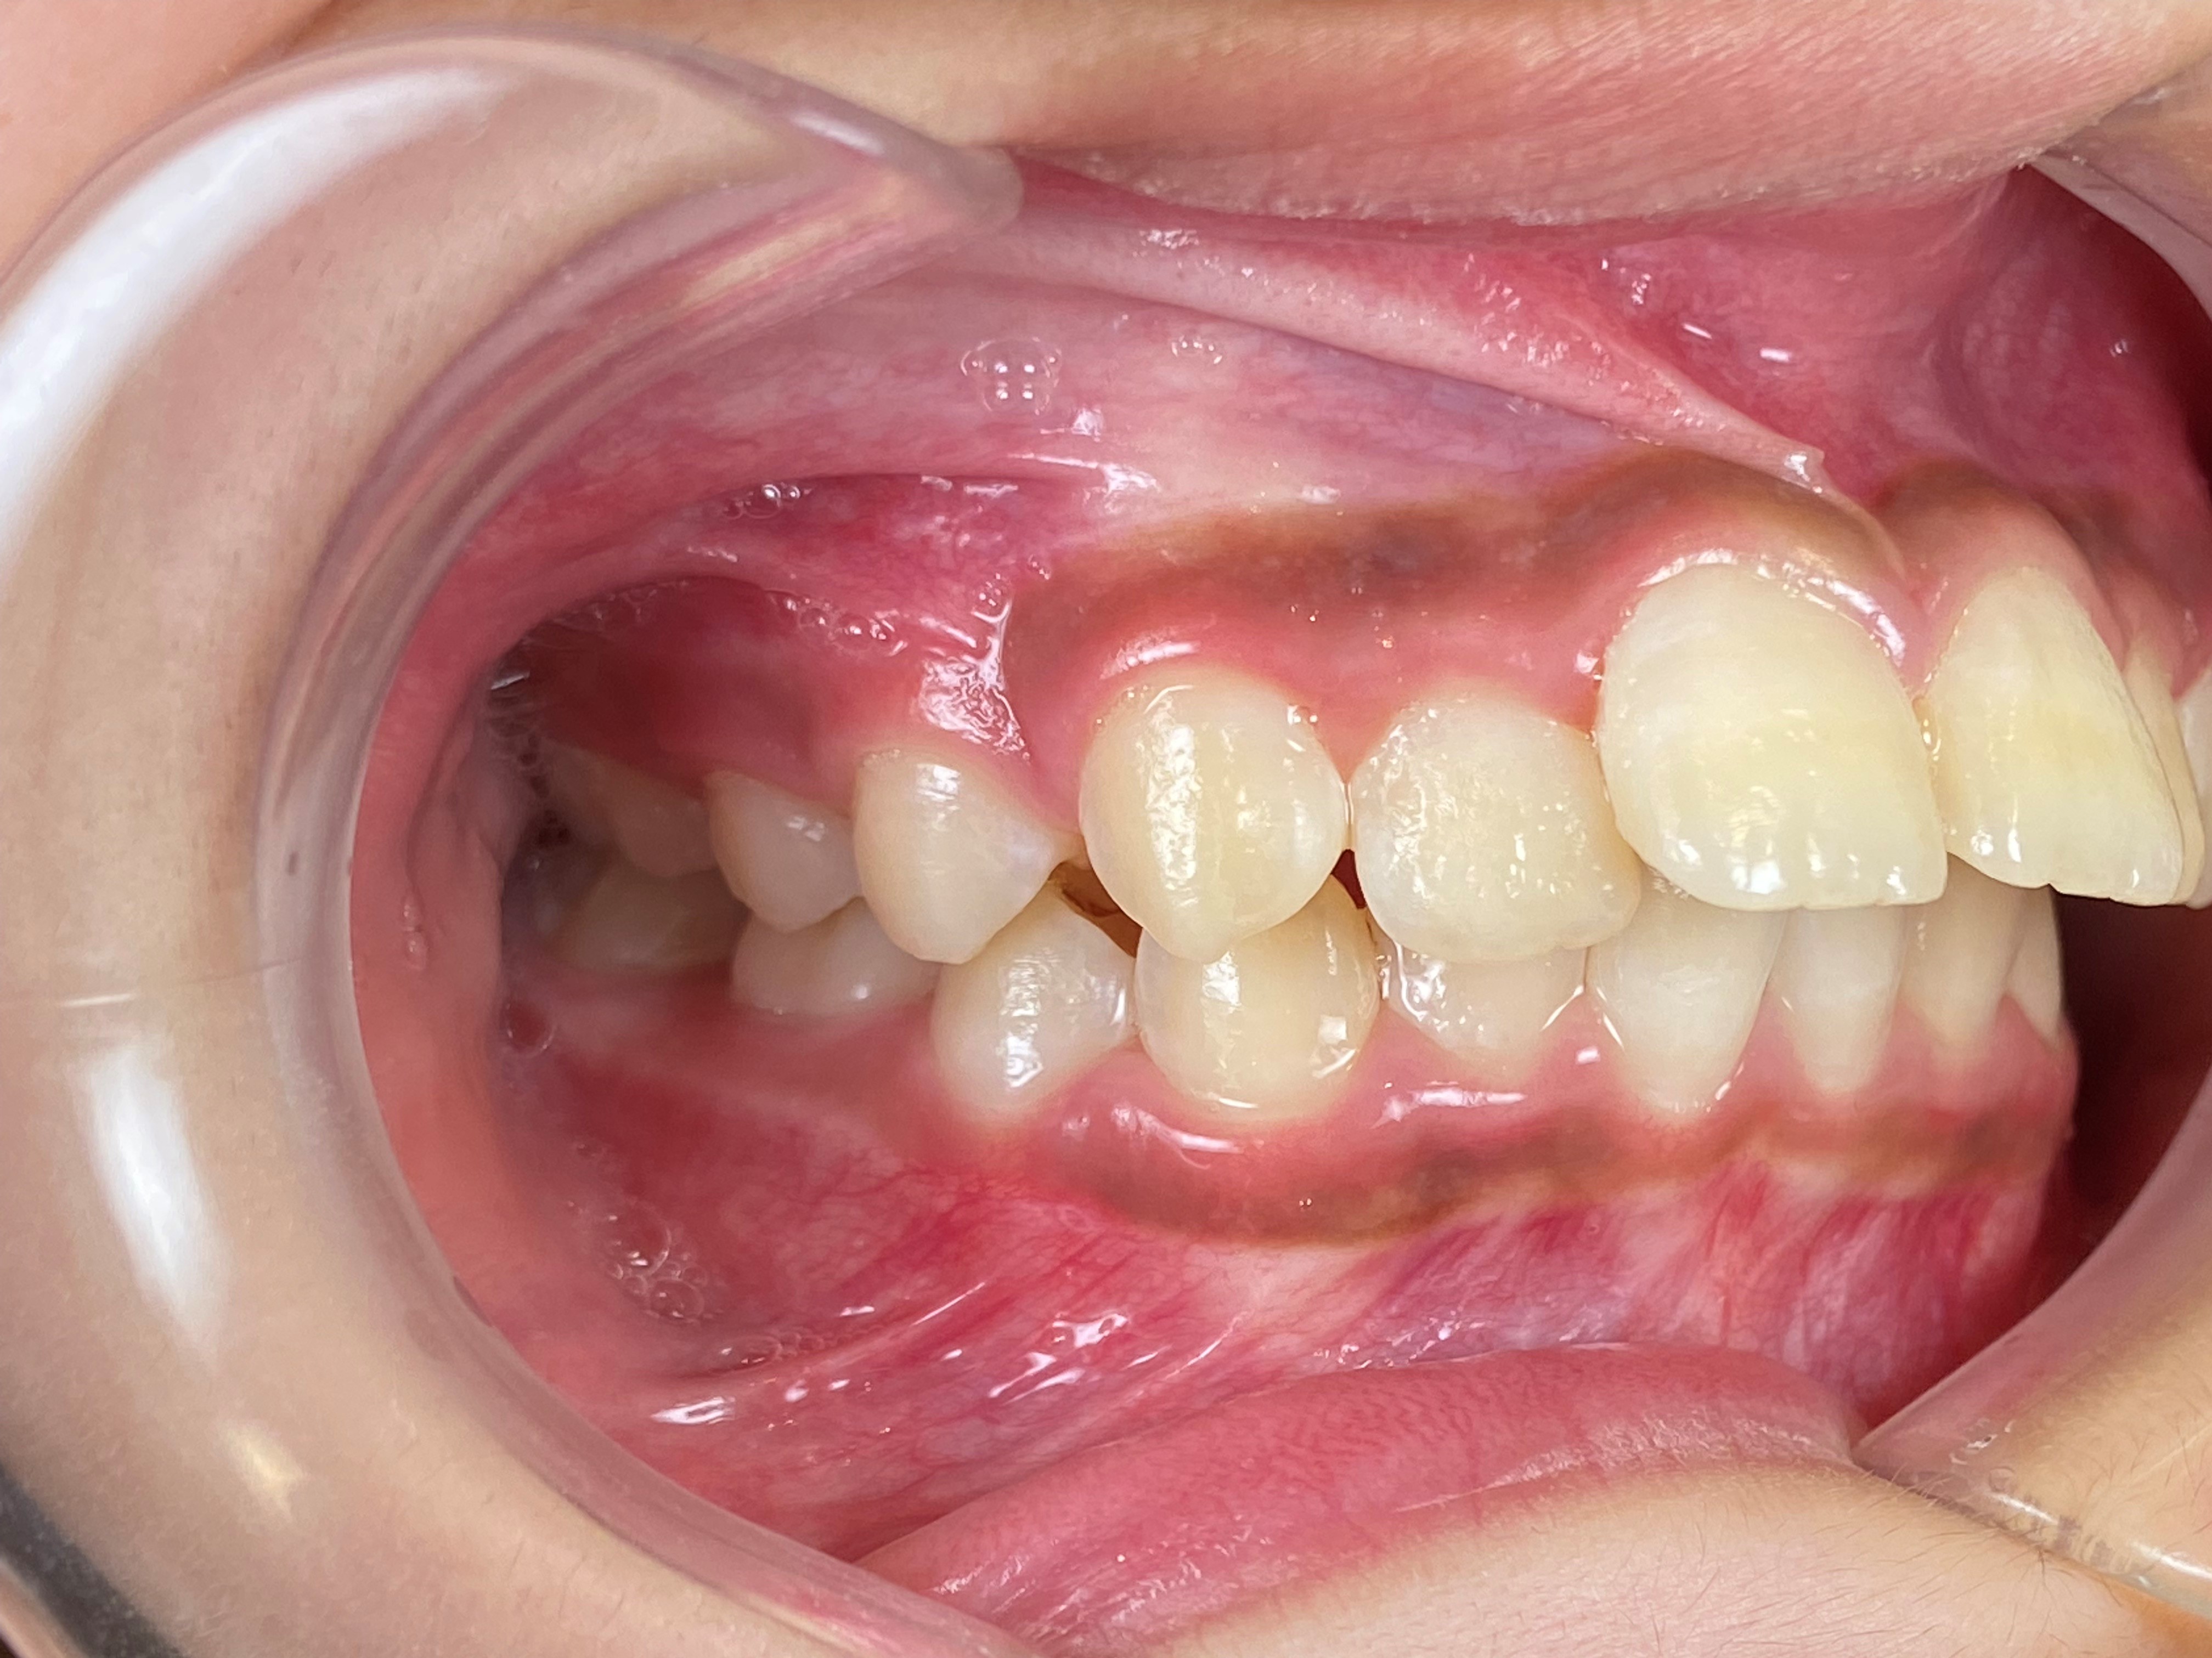

プレオルソ症例|下の前歯が出ているのが気になる

2026/03/24 小児矯正